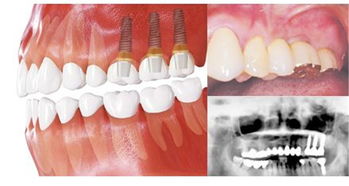

種植牙不僅哭恢復(fù)我們的咀嚼功能,而且還可以很好的保證我們牙齒的外觀形態(tài),從而達(dá)到以假亂真的效果,但是,種植牙在好也屬于假牙,假牙再好也不如我們的真牙,因此,在進(jìn)行完種植手術(shù)以后我們一定要注意一下幾種情況: